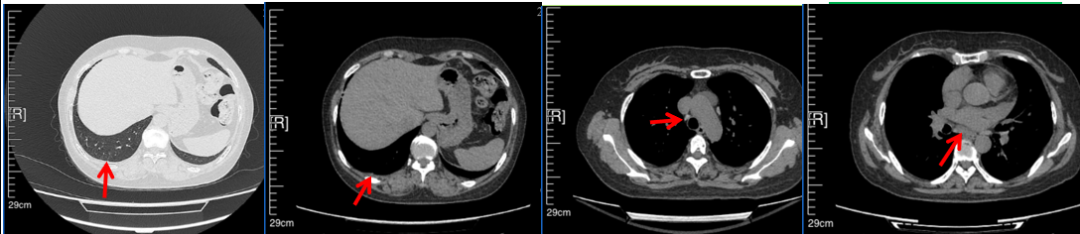

2016年1月复查CT提示支气管截断可见新发小结节,一线治疗采用培美曲塞+DDP方案化疗4周期(培美曲塞3.36,DDP 480mg)。化疗后复查胸部CT:右肺见不规则结节样影,最大层面大小约19mm*8mm,较前比较明显增大,疗效评估PD。2017.3-2017.4予单药多西他赛化疗3周期,疗效评估SD。2018年5月末复查CT提示结节较前增大,评效为PD,2018年6-10月予多西他赛+CBP化疗4周期,疗效评估SD。2022年5月患者出现活动后气短,复查胸部CT示右肺膨胀不良;右侧胸腔积液增多。胸腔积液包埋病理示符合肺腺癌细胞。行NGS基因检测:EML4:exon13-ALK:exon20融合。PD-L1(克隆号22C3)TPS<1%。

2022.05

2022.08

2023.05

2024.12